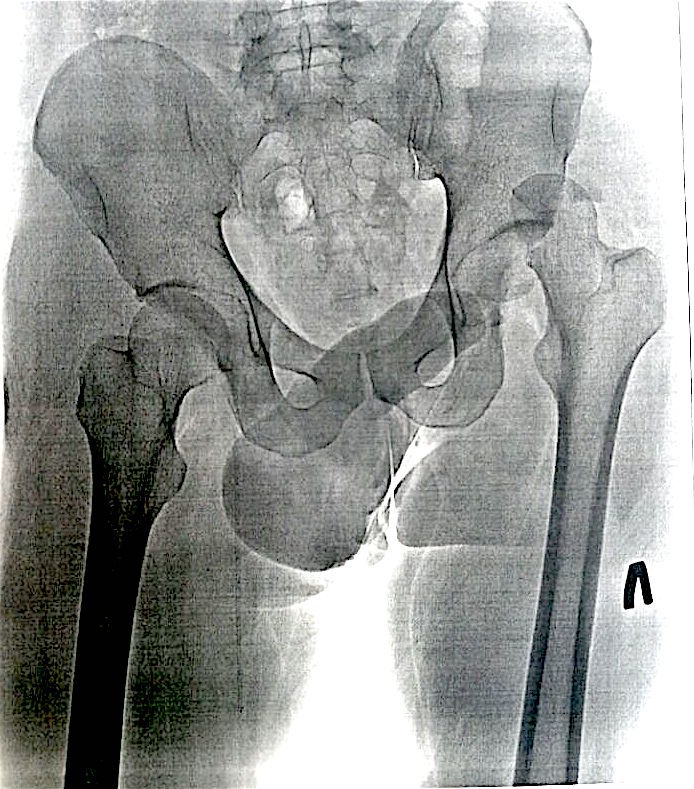

Травматический вывих левого бедра с переломом головки бедренной кости

Травматический вывих левого бедра с переломом головки бедренной кости, произведено открытое вправление, репозиция перелома головки бедренной кости с применением костной аллопластики материалом «Лиопласт».